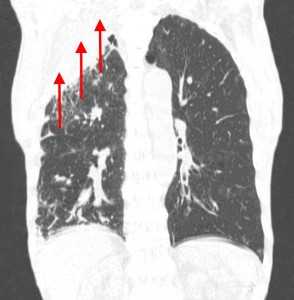

Гематогенные метастазы наиболее часто локализуются в периферических отделах легких, вдали от крупных сосудисто-бронхиальных пучков, вблизи плевральной оболочки. При множественных поражениях гематогенного характера наблюдается тенденция к увеличению количества очагов в направлении «сверху-вниз». Чаще гематогенные метастазы расположены хаотично, вне четкой связи с бронхами и видимыми легочными сосудами. Практически не бывает такого, чтобы гематогенные вторичные узлы находились только с одной стороны, или занимали только одну долю или сегмент. При наличии такого распределения в первую очередь нужно думать о туберкулезе (верхние доли), множественных абсцессах и т. д.

Лимфогенные метастазы проявляются увеличением лимфатических узлов средостения в сочетании с мелкоочаговой диссеминацией с очагами до 2-3 мм в диаметре вблизи плевры и в междольковых перегородках, а также по ходу бронхов и сосудистых пучков.